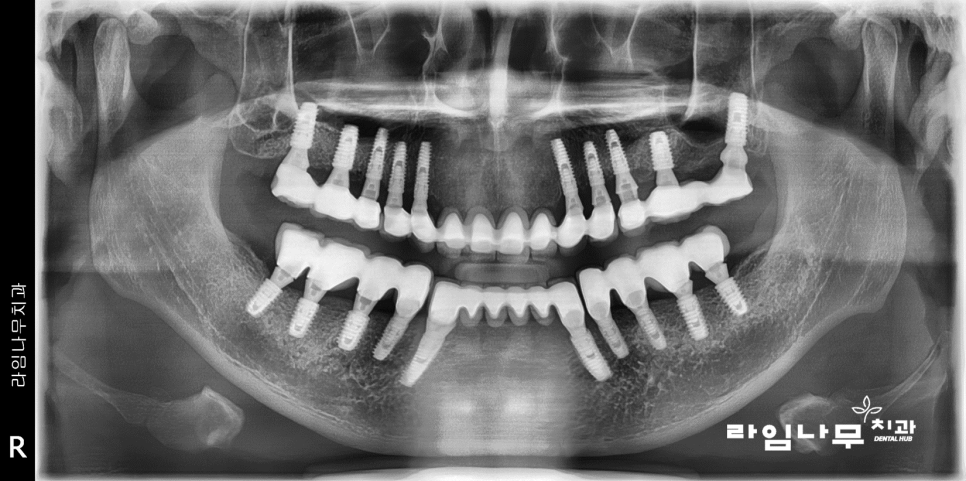

좋은 잇,몸,뼈를 만들고나서 총 20개의 임플란,트를 식립,

수개월의 시간을 거쳐 임프란트가

아주 잘 완성되었습니다!

#임플란트크라운 중 가장 기본적인

안쪽은 메탈, 겉은 포세린으로 치아와 유사한

PFM크라운을 선택하셨기 때문에

겉으로 볼 때는 치아색이며

안쪽에는 약간의 메탈이 보일 수 있습니다.

어금니쪽에 보이는 작은 Hole 들은

지난 포스팅에서 설명드린 #임플란트레진홀 이예요~

치조골의 상태도 많이 호전되었음을

엑스레이를 통해 확인할 수 있습니다.